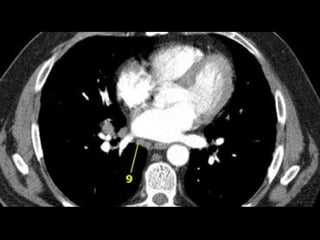

• 29.

9. Pulmonary ligamentLNs • Pulmonary ligaments are inferior extension of mediastinal pleural reflections that surround the hila. • Pulmonary ligaments LNs are located posterior and inferior to the inferior pulmonary veins.